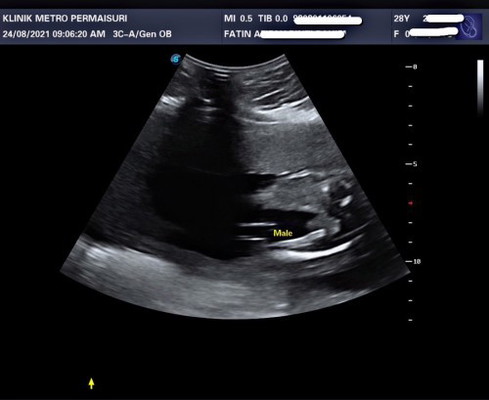

GENDER BABY BOY OR GIRL?

Hi mommies, nak tanya scan ni sure ke nampak baby boy ya? Sy baru buat detail scan semalam. Nak make sure utk mommies yg dah ada experience since ni my first baby. Is it really pistol? 😅 takut je beli baju boy then keluar nanti girl, tapi sy beli jg baju unisex before tau gender dia. TQ in advance! #pleasehelp #1stimemom #firstbaby #boyorgirl